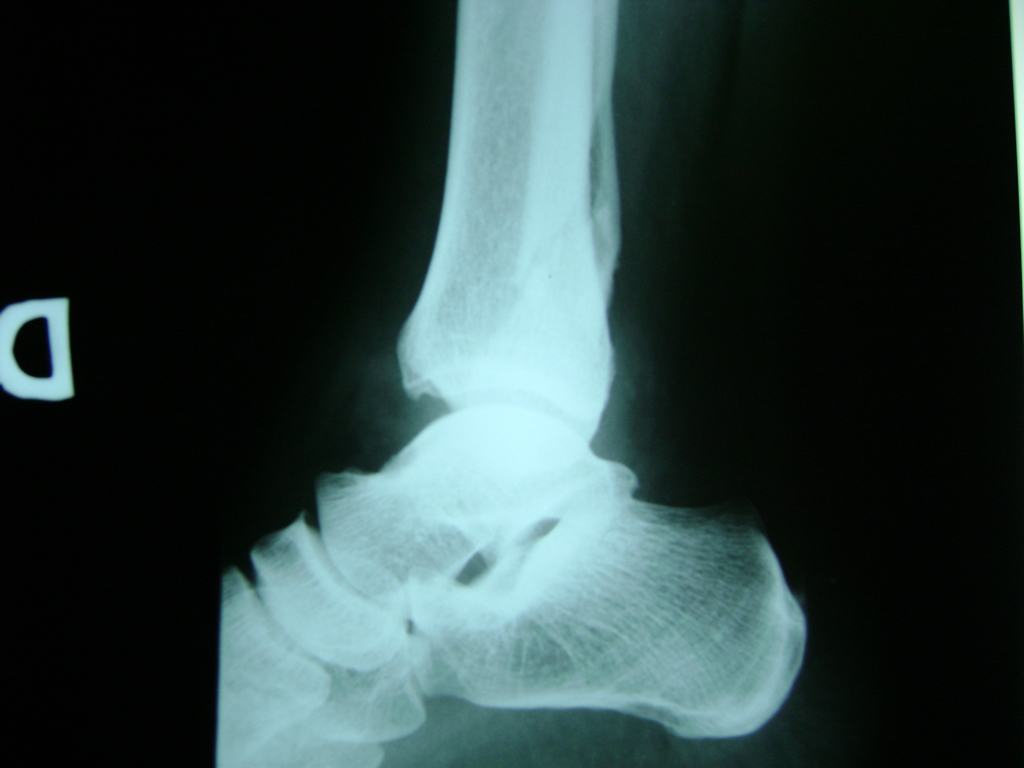

Una fractura de tobillo es la rotura de uno o más de los huesos del tobillo. Estas fracturas pueden ser:

Algunas fracturas de tobillo pueden requerir cirugía si:

- Los extremos de los huesos están desalineados entre sí (desplazados).